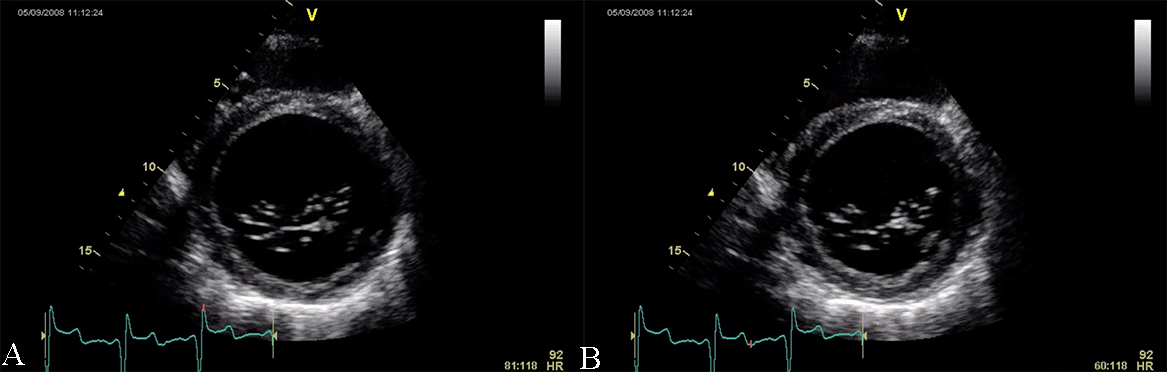

The causes of RCM can be classified as non-infiltrative (familial) or infiltrative (storage diseases), but the same pattern can be found in other disorders like diabetic cardiomyopathy, scleroderma, and endomyocardial fibrosis [38, 39, 40]. An accurate myocardial investigation by MRI and myocardial scintigraphy allows the diagnosis of different types of myocardial amyloidosis which is increasingly observed in the elderly either by transthyretin (aTTR) or by AL–light immunoglobulin chains in different plasmacytomas [41]. Another type of RCM is found in sarcoidosis and it can cause global or regional LV wall motion abnormalities. In some cases, the changes are specifically revealed on the basal posterior and lateral wall of the LV [42, 43, 44]. The most common finding is myocardial thinning, but RCM can also present with hypertrophy or it can include myocardial aneurysms [38, 45, 46, 47]. In some RCMs such as endomyocardial fibrosis or hypereosinophilic syndrome apical intraventricular thrombosis may be recognized; this may be responsible for pulmonary or systemic cardioembolism [48]. In RCM due to amyloidosis, apart from hypertrophy and wall motion abnormalities (Fig. 9), valvular involvement may also be noted with thickened aortic cusps or mitral leaflets determined by local deposition of amyloid [49].

Fig. 9.The echocardiographic aspect of cardiac amyloidosis, associated with aortic stenosis. (A) short-axis view, showing left ventricular hypertrophy. (B) Speckle tracking echocardiography obtained by measuring longitudinal strain in apical 4 chamber view, shows a significantly reduced GLS (global longitudinal strain) of –8.6%.